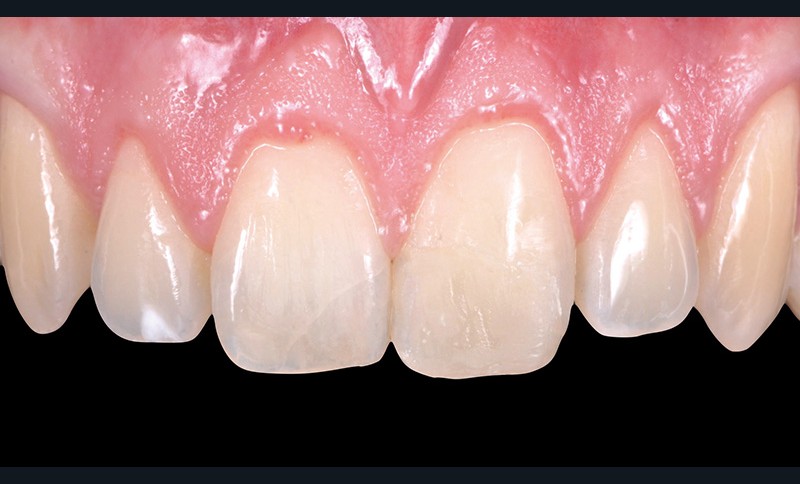

1. Situation initiale. Le composite a été refait trois fois durant

les deux dernières années, du fait de décollements répétés. La forme et le poli de surface sont à l’évidence perfectibles ; pourtant l’intégration du composite est correcte ! Cela prouve une nouvelle fois l’incroyable potentiel esthétique de ce matériau !